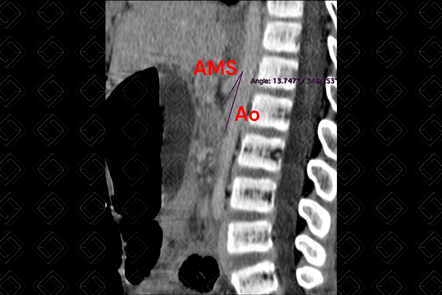

Texto alternativo para a imagem Figura 1. Créditos: Dra. Elazir Mota - Rio de Janeiro/RJ

Descrição da figura 1: Ângulo aortomesentérico inferior a 22 graus, medido no plano sagital.

• Tomografia computadorizada do abdome: D iante desta suspeita, deve sempre ser realizado após a administração do contraste venoso. Existem dois indicadores tomográficos da síndrome que são o ângulo aortomesentérico inferior a 22 graus, medido no plano sagital (figura 1 ) e a distância aortomesentérica, medida no plano axial, inferior a 8 mm (figura 2) . Além disso, observa-se distensão da primeira e segunda porções duodenais, bem como do estômago.